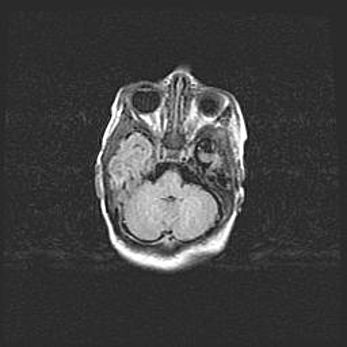

Подострая гематома правой гемисферы мозжечка.

Наружная гидроцефалия.

Возраст: 15 дней

Вес: 3100 г

Пол: женский

Окружность головы: 37 см

Срок гестации: 35-36 недель

При открытой наружной форме гидроцефалии у новорожденных расширяются и переполняются субарахноидные пространства.

Кровоизлияния в мозжечок имеют две клинико-анатомические формы: полушарные гематомы и кровоизлияния в червь.

К появлению этой патологии может привести: повреждения головного мозга, возникающие в результате асфиксии и гипоксии плода при беременности, или травмы во время родов. Редко гематома мозжечка может быть результатом первичной коагулопатии и сосудистой мальформации, диссеминированном внутрисосудистом свертывании, изоиммунной тромбоцитопении.